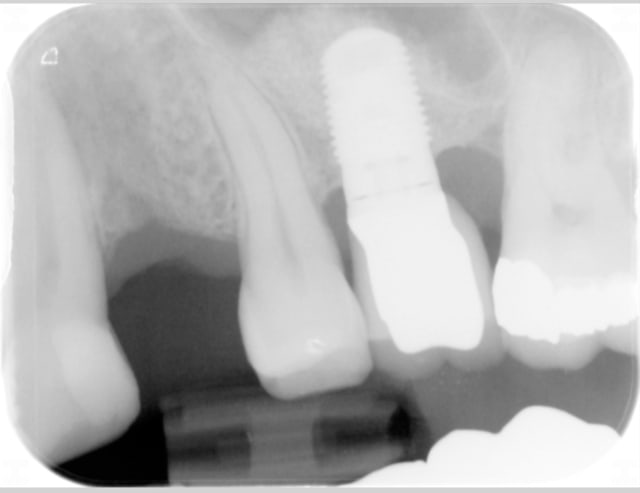

Le cas date de 2010, le sinus est traité par élévation crestale + mise en place de 2 mb de PRF dans le "trou" avant de combler au RTR et en dernier os récupéré du forage pour espérer qu'il reste contre l'implant.

J'ai pas pu enlever le prénom mais vous avez les dates dans l'ordre

La radio postée hier est un "contrôle à 6 ans avant d'implanter en 14

Qu'est-il arrivé à la 23? Elle présentait un soin mal adapté en 2009, puis a été couronnée en 2010, et aujourd'hui, plus rien, disparue...

comme tu le vois sur la première radio du premier post, elle va bien avec un composite distal